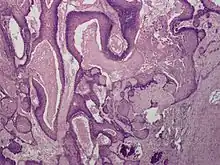

| Proliferating tricholemmal (pilar) cyst | |

Proliferating trichilemmal cysts (also known as a "Pilar tumor", "Proliferating follicular cystic neoplasm", "Proliferating pilar tumor", and "Proliferating trichilemmal tumor"[2]) are a cutaneous condition characterized by proliferations of squamous cells forming scroll-like structures.[2][3]: 678